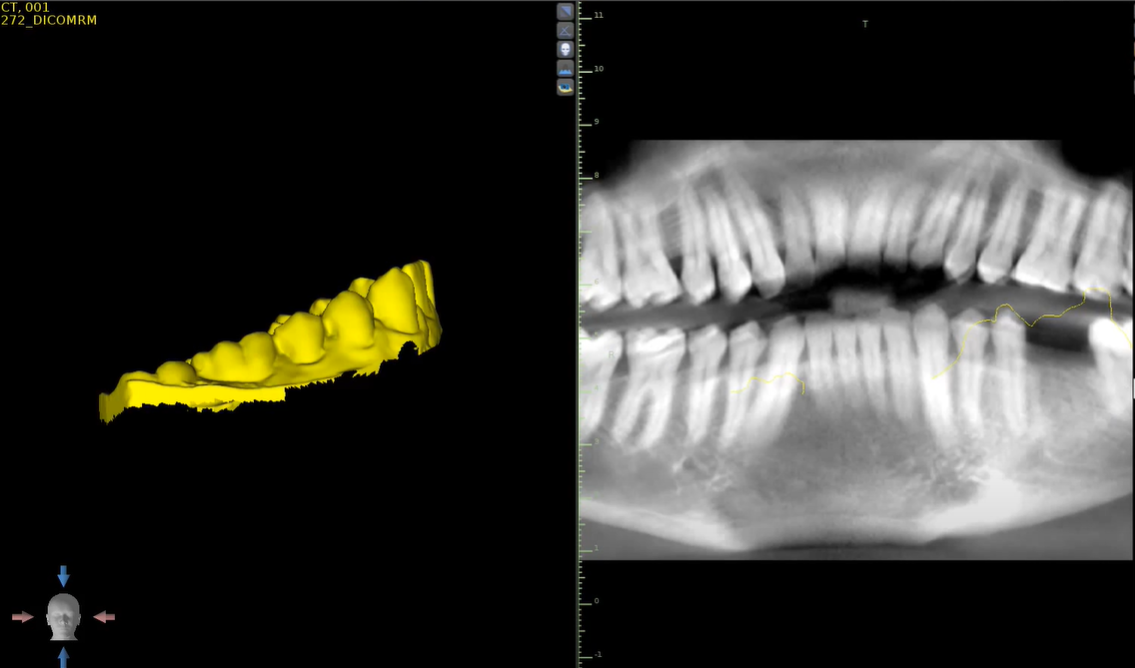

L'ortopantomografia o, più comunemente, “radiografia panoramica delle arcate dentarie”, è un esame radiologico che permette in modo non invasivo e non doloroso lo studio delle arcate dentarie e delle ossa mandibolari.

La Cone Beam 3D è una moderna metodologia diagnostica che consente di riprodurre sezioni o un'immagine del cranio tridimensionale che viene utilizzata, in genere, per l'implantologia.

Telecranio Latero-Laterale viene utilizzato per la progettazione ortodontica in tutti i tipi di pazienti, in particolare per i bambini.